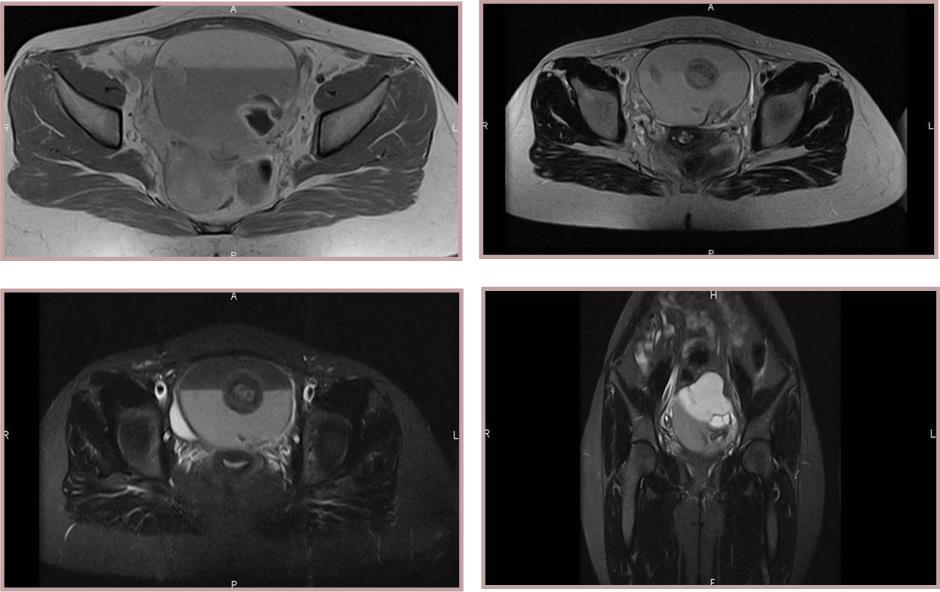

Figure 1(a,b,c,d ).Two lesions within cystic component measuring 6 x 7 x 8 cm. MRI reveals a large and well-defined encapsulated tumour. Two solid components with an intermediate signal in T2 and T1 with a moderate contrast enhancement on T1 weighted.

Two lesions within cystic component measuring 6 x 7 x 8 cm. MRI reveals a large and well-defined encapsulated tumour. Two solid components with an intermediate signal in T2 and T1 with a moderate contrast enhancement on T1 weighted.